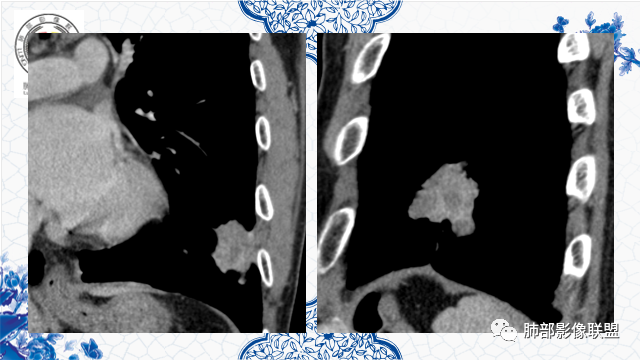

3月前左肺中下野可见结节灶,现CT可见沿支气管走形融合成团片灶,近端支气管进入后截断,病灶整体以平直收缩为主,局部膨隆,与胸膜呈糊墙样改变,病灶周边可见结节,总体分析病灶是结节融合形成,远端大近端小,符合支气管爬行征,强化后其内可见多发低强化区,低强化边界不清,其内未见血管,首先考虑炎性病灶结核,隐球菌分布不符合,但是也可以有,另外恶性不能排除,建议排查结核、隐球菌,如不能明确,穿刺活检是必要的!

第四,有支气管爬行的感觉。

第五,专门提出三个月前胸片多发小结节,三个月后变大成肿块。